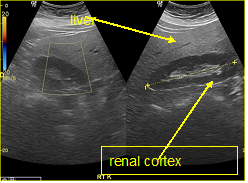

In a 4-years period (from 2016 to 2019) a retrospective study of 887 patients with fatty infiltration of the liver was performed, out of which 608 were males and 272 were females, aged 42 to 69 and 7 obese children (age from 8 to 13 years). All patients were examined in the ultrasound cabinet of our hospital (hospitalized, regular appointments and emergency incidents) and subjected to upper abdominal ultrasound scan, with convex transducer 4C MHz, in three ultrasound imaging planes: transverse, oblique and sagittal planes.5−7 In order to better depict the liver, especially in obese patients or those with excessive intestinal gas, the patients were asked to inhale deeply and hold their breath for the duration of the ultrasonographic examination for a few seconds at a time, so that the liver could be visible in its entirety. The ultrasound examination revealed the echogenicity of the parenchyma of the liver and was compared with the parenchyma of the right kidney, the spleen and the pancreas (Figure 1−3). Τhere is always the risk of missing a diagnosis of mild hepatic steatosis on ultrasound if there is concurrent chronic renal disease, which increases the echogenicity of the kidneys (Figure 4), if there is any doubt that the patient might have a chronic renal disease, comparison of the liver to the left kidney and the spleen may be useful.8

Figure 4 Chronic renal diseases, which increase the echogenicity of the kidneys.